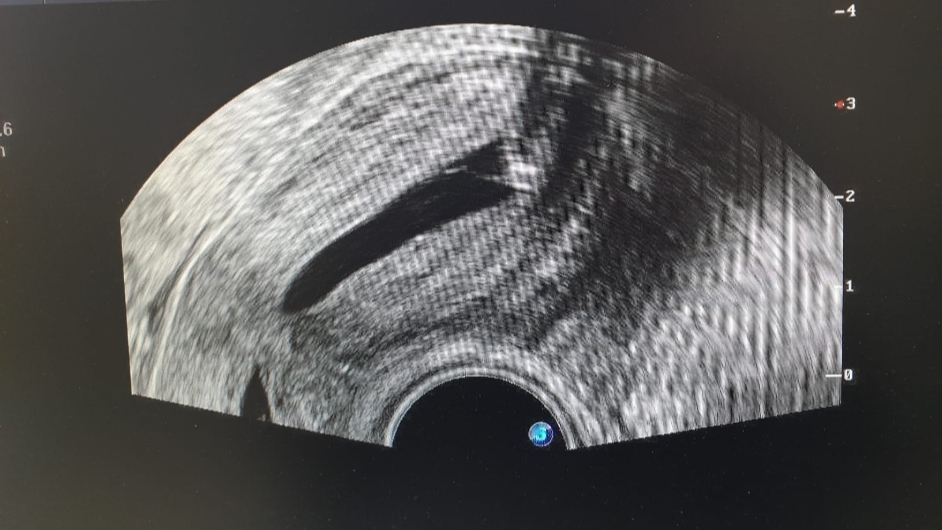

Meine KiWu hat mir vor dem Transfer eine Hydrosonographie empfohlen, diese heute morgen getätigt mit dem Ergebnis: Da ist etwas, was nicht sein sollte. Mehr würde ich aber erst erfahren bei der Spezialistin, diese hätte aber erst Mitte Januar Zeit.

Bilder angehängt